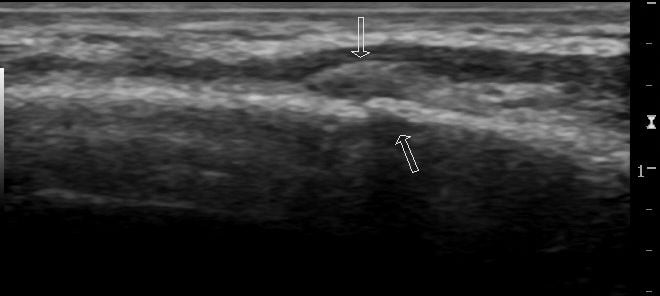

Figure 3:

Longitudinal view demonstrating a cortical break with overlying crescent shaped hematoma of the same rib fracture as figures 1 and 2.

The example images and annotations are courtesy of Dr. Maulik S Patel, Radiopaedia.org. From the case rID: 16479